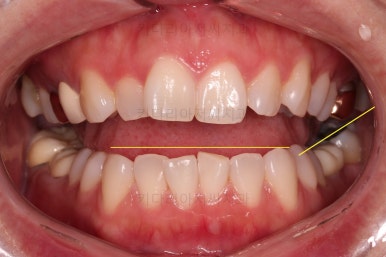

앞니 부분교정으로 치료계획을 세웠는데 다른 분들에 비해 난이도가 높은 치료가 예상되었던 이유는 우측 상단의 사진에 선 그어놓은 부분을 보시면 어금니에 비해 아래앞니가 약간 솟구쳐 높이가 맞지 않다는 점이었어요.

이 부분을 개선하기 위해 일반적인 부분교정 외에 추가적인 장치가 필요했었습니다.